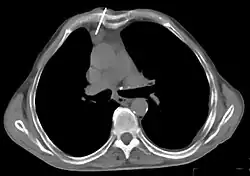

Présentation tomodensitométrique classique d'un thymome à un stade précoce (cercle rouge). À l'arrière, l'aorte, la veine cave supérieure et l'artère pulmonaire sont visibles en coupe.